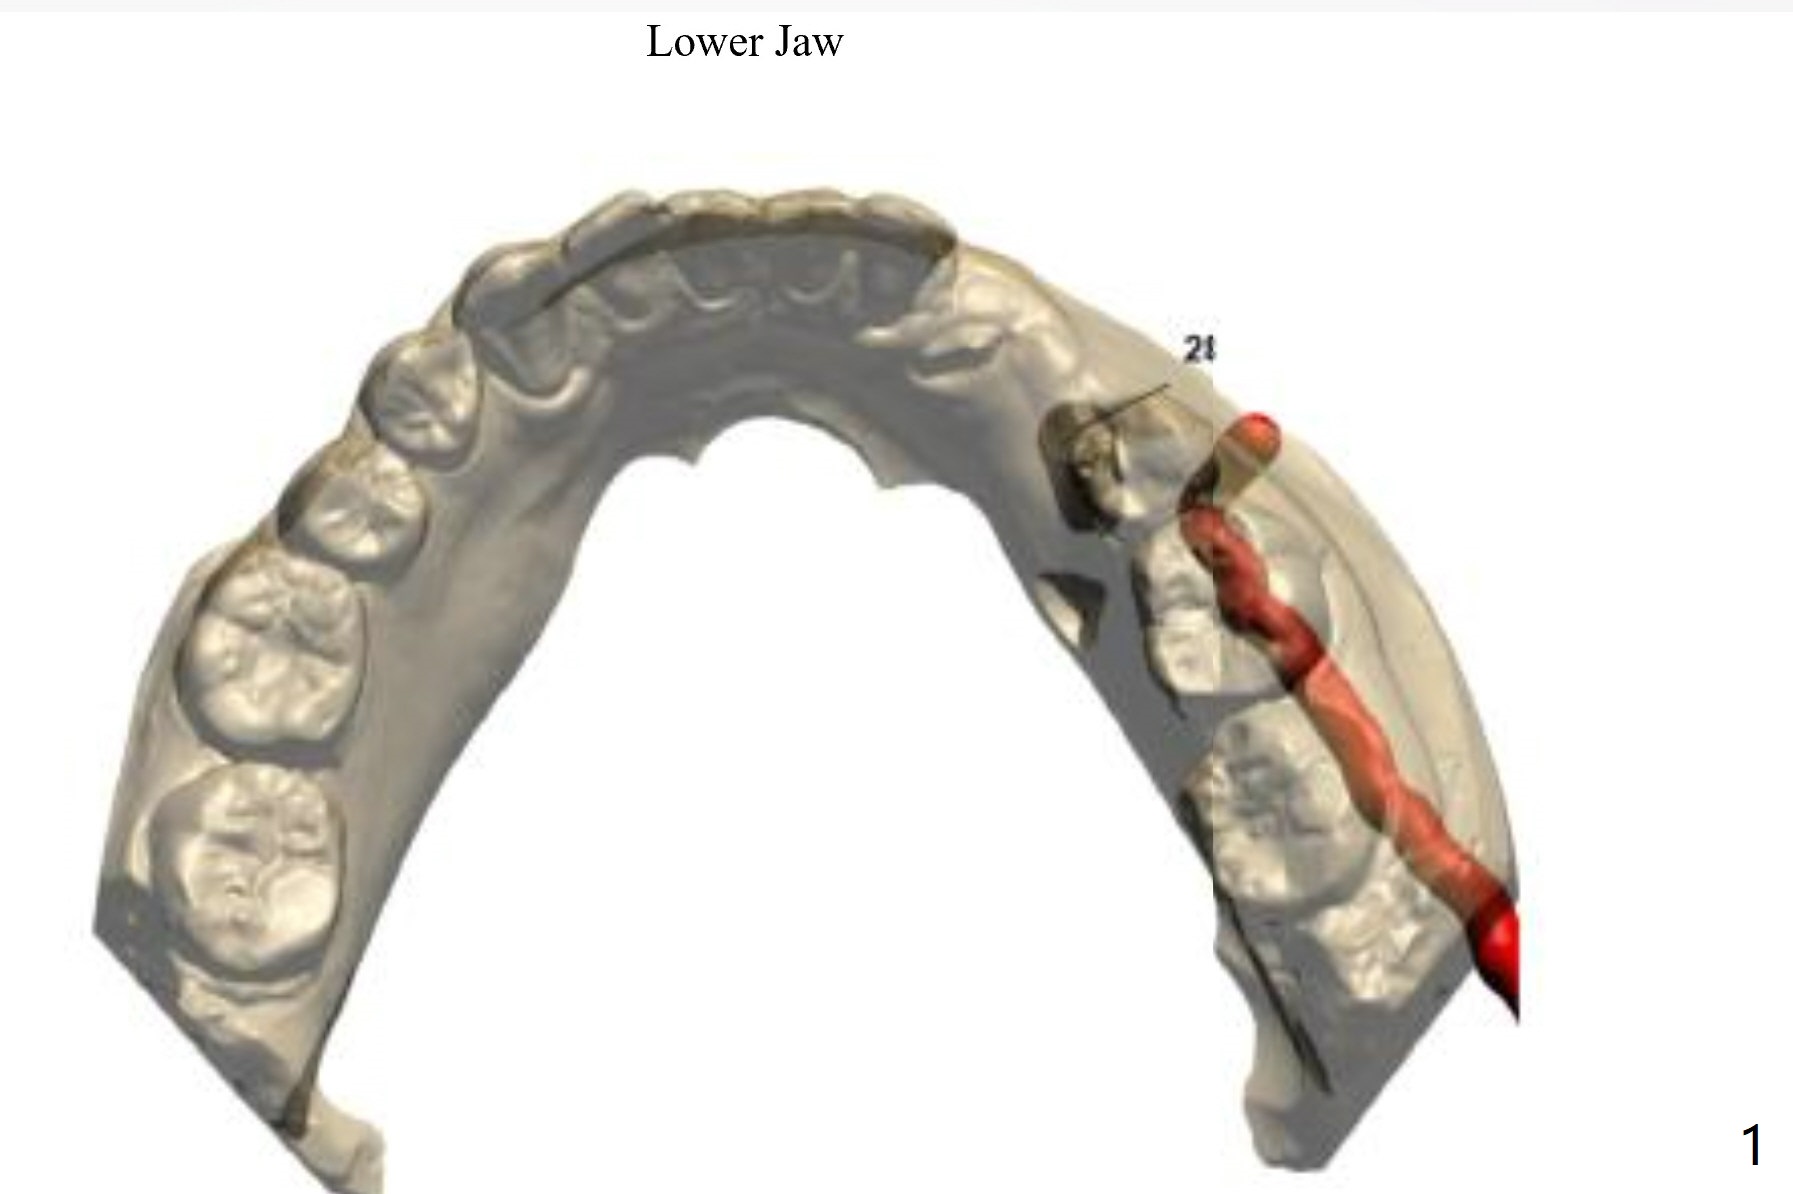

A 30-year-old man had the tooth #28 extracted with no bone graft. Allograft will be placed post implantation.

Lower Premolar

Immediate Implant,

Trajectory